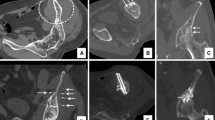

Fractures/osteolysis occurring in the anterior part of the sacral ala and associated with functional impairment can be treated with percutaneous cementoplasty (sacroplasty), as compression is the dominant stress in this location (Fig. 5A–C). Sacroplasty is superior to non-surgical management to restore patient mobility in case of sacral insufficiency fracture, a frequent condition in cancer patients [35, 36]. A recent meta-analysis involving more than 800 patients reported the effectiveness of sacroplasty to manage osteoporotic and malignant sacral fractures, with sustained benefits at 12 months [37]. Alternatively to cement injection, screw fixation of insufficiency/pathological fractures of the sacral ala has demonstrated good functional results requiring a trans-iliac approach in order to approach the fracture line perpendicularly [2, 38]. Based on cadaveric and finite element models, the strongest fixation technique seems to be obtained with the insertion of 2 parallel screws (i.e. that each screw goes through the right and left sacro-iliac joints), one in S1 and one in S2 [39, 40]. Because of the underlying bone fragility, the authors usually recommend augmenting the anchorage of the tip of the screws with cement, in order to prevent screw loosening and dislodgement [28, 29]. There has been no study to date comparing screw fixation and sacroplasty for the management of non-displaced fractures of the sacral ala. Osteolysis/fracture of the posterior and upper part of the sacro-iliac joint decreases the resistance to tension and shear leading to failure of the strong posterior ligamentous support increasing the risk of pelvic instability. In this situation, cementoplasty might not be sufficient due to poor resistance to shear forces and trans-sacroiliac screw fixation seems mandatory to prevent biomechanical failure, provided that the screws can be anchored in normal trabecular/cortical bone (Fig. 5D–F) [23]. Cement augmentation of the screws in the setting of advanced osteolysis may reduce failure of the fixation [9, 28, 29]. There is limited evidence to support prophylactic stabilization of asymptomatic sacro-iliac lesions, especially if there is no cortical disruption or involvement of the posterior and superior part of the sacro-iliac joint [1].

Consolidation of sacro-iliac lesions in patients with mechanical pain. A Axial CT scan at the level of S1–S2 demonstrates an osteolytic lesion (asterisks) at the intermediate and anterior part of S1 and the right sacral ala. B CT at the L5–S1 level: there is no destruction of the superior and posterior part of the sacral ala. C The risk of fracture and failure to shear can be considered low: stand-alone cementoplasty was performed to provide resistance to compression. D Axial CT scan at the S1–S2 level in another patient shows bilateral post-radiation fractures of the sacrum (arrowheads). E The fracture is extending cranially with complete disruption of the posterior and superior part of the sacral ala, exposing to shear forces. F The fractures were stabilized with two trans-sacro-iliac screws (one in S1 and one in S2) with additional cement injection to improve the anchorage of the screws